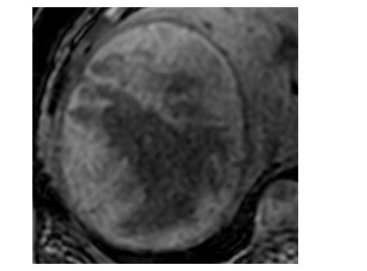

A 3T MRI with hepatobiliary specific contrast (Gd-BOPTA) scan was performed and it showed a heterogeneous mass in the right lobe of liver measuring ~15cms in diameter on T2WI (Figure 11A and B), well defined and well encapsulated. It showed heterogeneous focal vascular enhancement on the arterial phase (Figures 12 and 13);similar to aorta and areas of further enhancement on the portal-venous phase (Figure 14) and the delayed images (Figure 15).On the hepatobiliary phase (Figure 16) after 90 mins; the mass is predominantly isointense to the adjacent liver parenchyma with few areas of hypointensity. No significant restricted diffusion with ADC drop was seen. The ADC value in the degenerated and non-degenerate areas was in the rang of 1.4 - 1.5 x10-3mm2/s.

| Figure 12: T1WI Axial image shows the mass to be predominanalty hyperintense with central hypointensity |